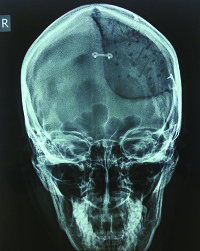

A 23-year-old woman presented at the University Hospital Osijek, Croatia, department of neurosurgery, with a benign change in the bones of her skull. The deformed part of the skull was on her forehead, and highly visible. In addition to needing to remove part of the diseased bone, doctors determined that it was also necessary to address the woman’s cosmetic defects in order to reduce the psychological consequences of the surgery.

A 23-year old woman’s successful cranioplasty using 3D printing technology.

Cranial surgeries such as this woman’s, require high precision and accuracy of the implant as well as compactness of the material in order to ensure successful sterilization of the mold. 3D prototyping models enable the hospital to remove any faults in the mold design in the early phases, before surgery.

“3D printing enables faster product development and easier communication with patients. This aids in early detection of faults and problems which makes the whole process faster and more economical,” said Sercer. The first step is converting a patient’s CT scan into a virtual 3D image. This prototype is 3D printed to check for an exact fit of the implant by measuring it against the bone cavity in the patient’s skull. Only once the exact measurements are confirmed is the mold filled with a low-viscosity PMMA, or bone cement, to create the actual prosthesis.